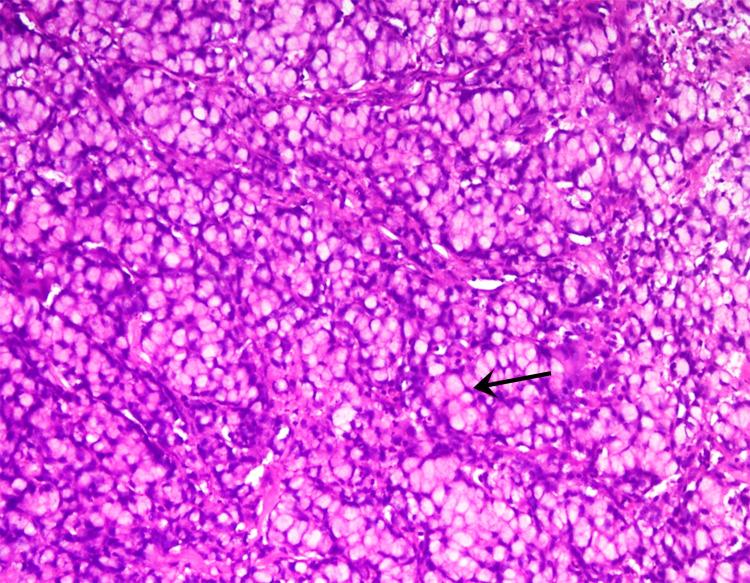

Periampullary carcinoma in adolescents is very rare and may be associated with hereditary syndromes. Pancreaticoduodenectomy (PD) in adolescents is rarely performed. The experience and results of pancreaticoduodenectomy in adolescents are not well reported. Here, we report a case of periampullary carcinoma, duodenal origin, signet ring type with microsatellite instability (MSI), in a 13-year-old male for which pancreaticoduodenectomy was successfully done.

青少年壶腹周围癌非常罕见,可能与遗传综合征有关。青少年很少进行胰十二指肠切除术(PD)。关于青少年胰十二指肠切除术的经验和结果报道较少。在此,我们报告一例13岁男性十二指肠起源的印戒型壶腹周围癌伴微卫星不稳定性(MSI),该患者成功接受了胰十二指肠切除术。